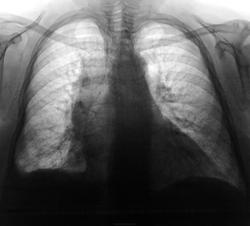

медиастенит, жидкость в правой плевральной полости

Думаю, что это спайки справа внизу и новообразование средостения...

Расширено вправо переднее средостение. Неужели тимома? Венозный компонент лёгочного рисунка, возможно, усилен…, качество изображения… увы.

учитывая поворот из за сколиоза, может вообще ничего не оказаться. Но думаю что медиастинальная плевра утолщена справа.

Однородность срединного затемнения, наличие затемнений в синусе, м/долевых щелях, честкость ировность контуров. Предположительно- осумкованный центральный плеврит.

На тимому уже больше похоже. Но и парамедиастинальное осумкование плевральногой экссудата небольшого объёма может быть.

Была у меня одна лаборантка, которая в свое время работала в Польше. Так там про нормальные ОГК говорили: плуцы в норме, сэрдце закоханэ. То бишь: легкие в норме, сердце влюбленное. Тут конечно легкие не в особой норме, но вся беда в сердце, а легкие вторичны.